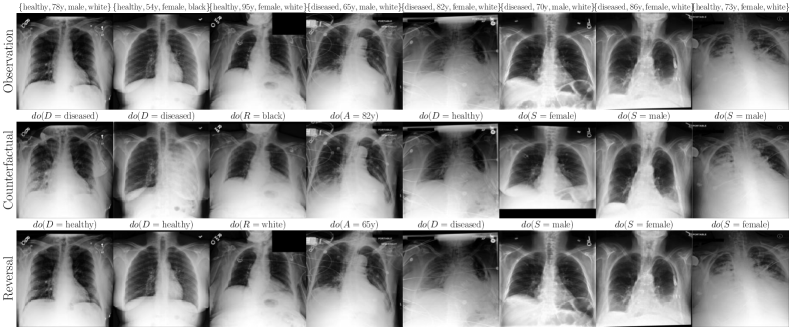

6.2 Case Study: Chest X-ray Imaging Counterfactuals

To extend our study to high-dimensional settings, we conduct experiments on MIMIC-CXR (Johnson et al., 2019), a widely used dataset for counterfactual inference. Our assumed causal graph follows the baselines (Ribeiro et al., 2023; Xia et al., 2024), and includes Sex (), Race (), Age () and Disease () variables, where , and cause the X-ray image . To parameterise our flow models, we use a streamlined version of Dhariwal and Nichol (2021)’s UNet architecture (see Appendix F for details). Table 2 and Figure 4 report our main results. We observe substantial improvements over baselines (Ribeiro et al., 2023; Xia et al., 2024) using our flows, across all three counterfactual soundness axioms, and without requiring any costly counterfactual fine-tuning or classifier(-free) guidance. That said, this alone does not imply causal validity. In Appendix F, we report additional comparisons and ablations. We observe performance trade-offs: for instance, OT-Flow (which assumes Markovianity) outperforms on race interventions but underperforms Flow on disease interventions, suggesting non-Markovian interaction effects or a subpar OT approximation. Notably, our Markovian OT coupling substantially improves over the Naive OT flow baseline.